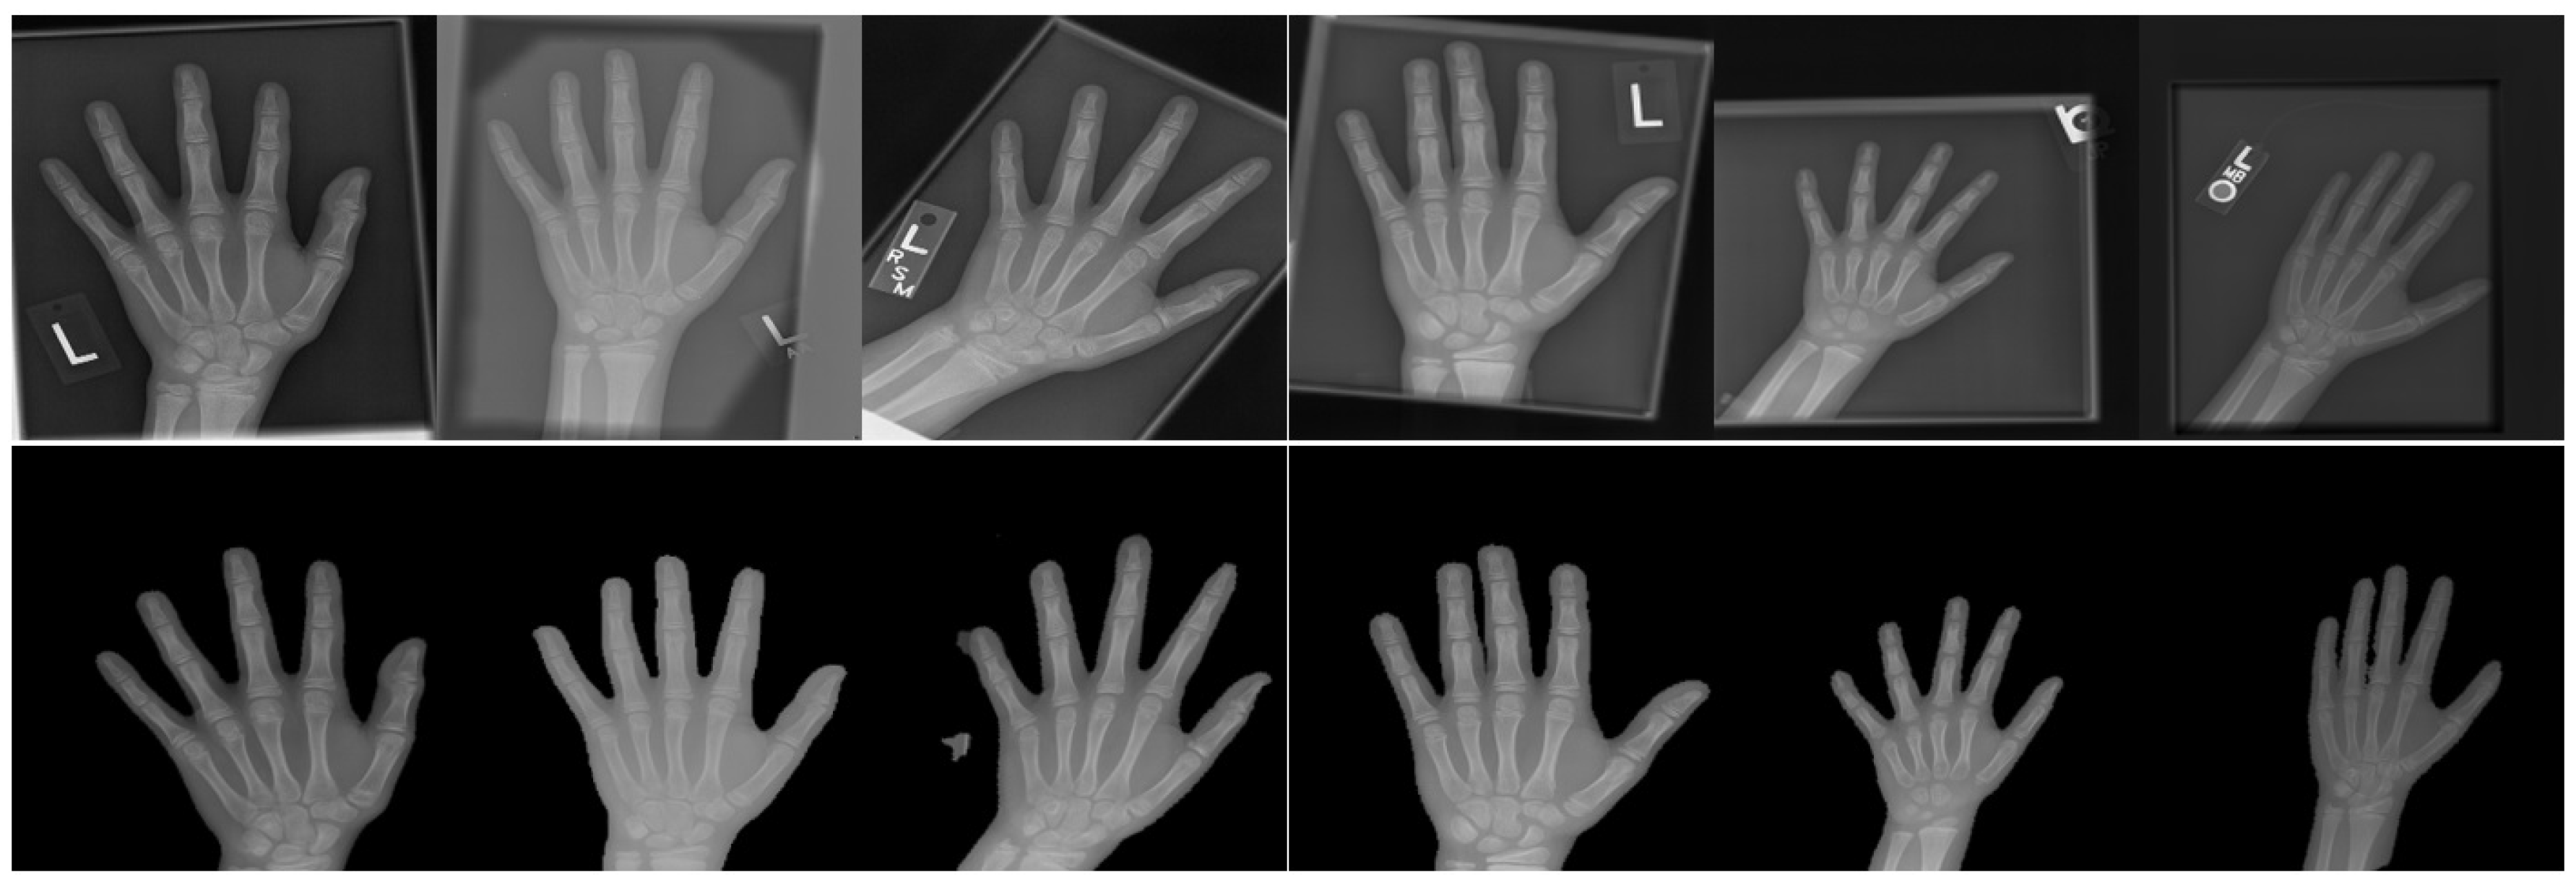

Examples of left hand bone age (BA) radiographs from four different

Examples of left hand bone age (BA) radiographs from four different Bone Age X Ray Report Regardless of the method used, an appropriate and standardized hand positioning procedure and radiographic image acquisition are required in order to better describe the skeletal maturation. — the bone age radiograph of the hand and wrist is a commonly performed examination to determine the radiographic age of the patient via the. Skeletal age determination is carried out for the. Bone Age X Ray Report.